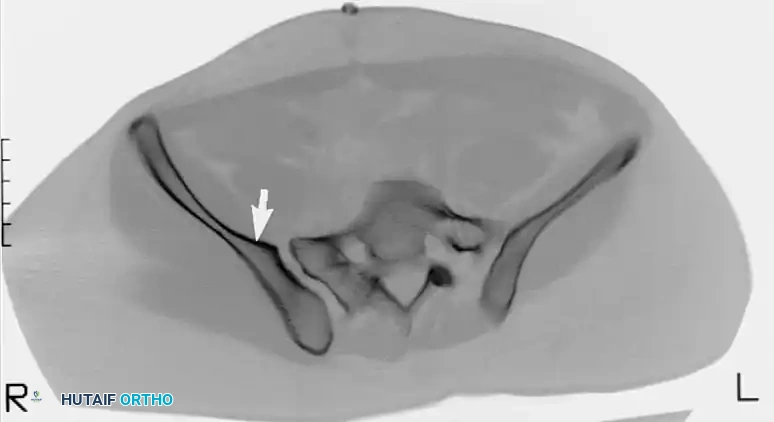

Image

CT scan demonstrating a recessed sacral ala (solid arrows) relative to the dense iliac bone adjacent to the sacroiliac joint—the iliac cortical density (ICD) (open arrow). Nerve roots are surrounded by fat within these recessed alae.